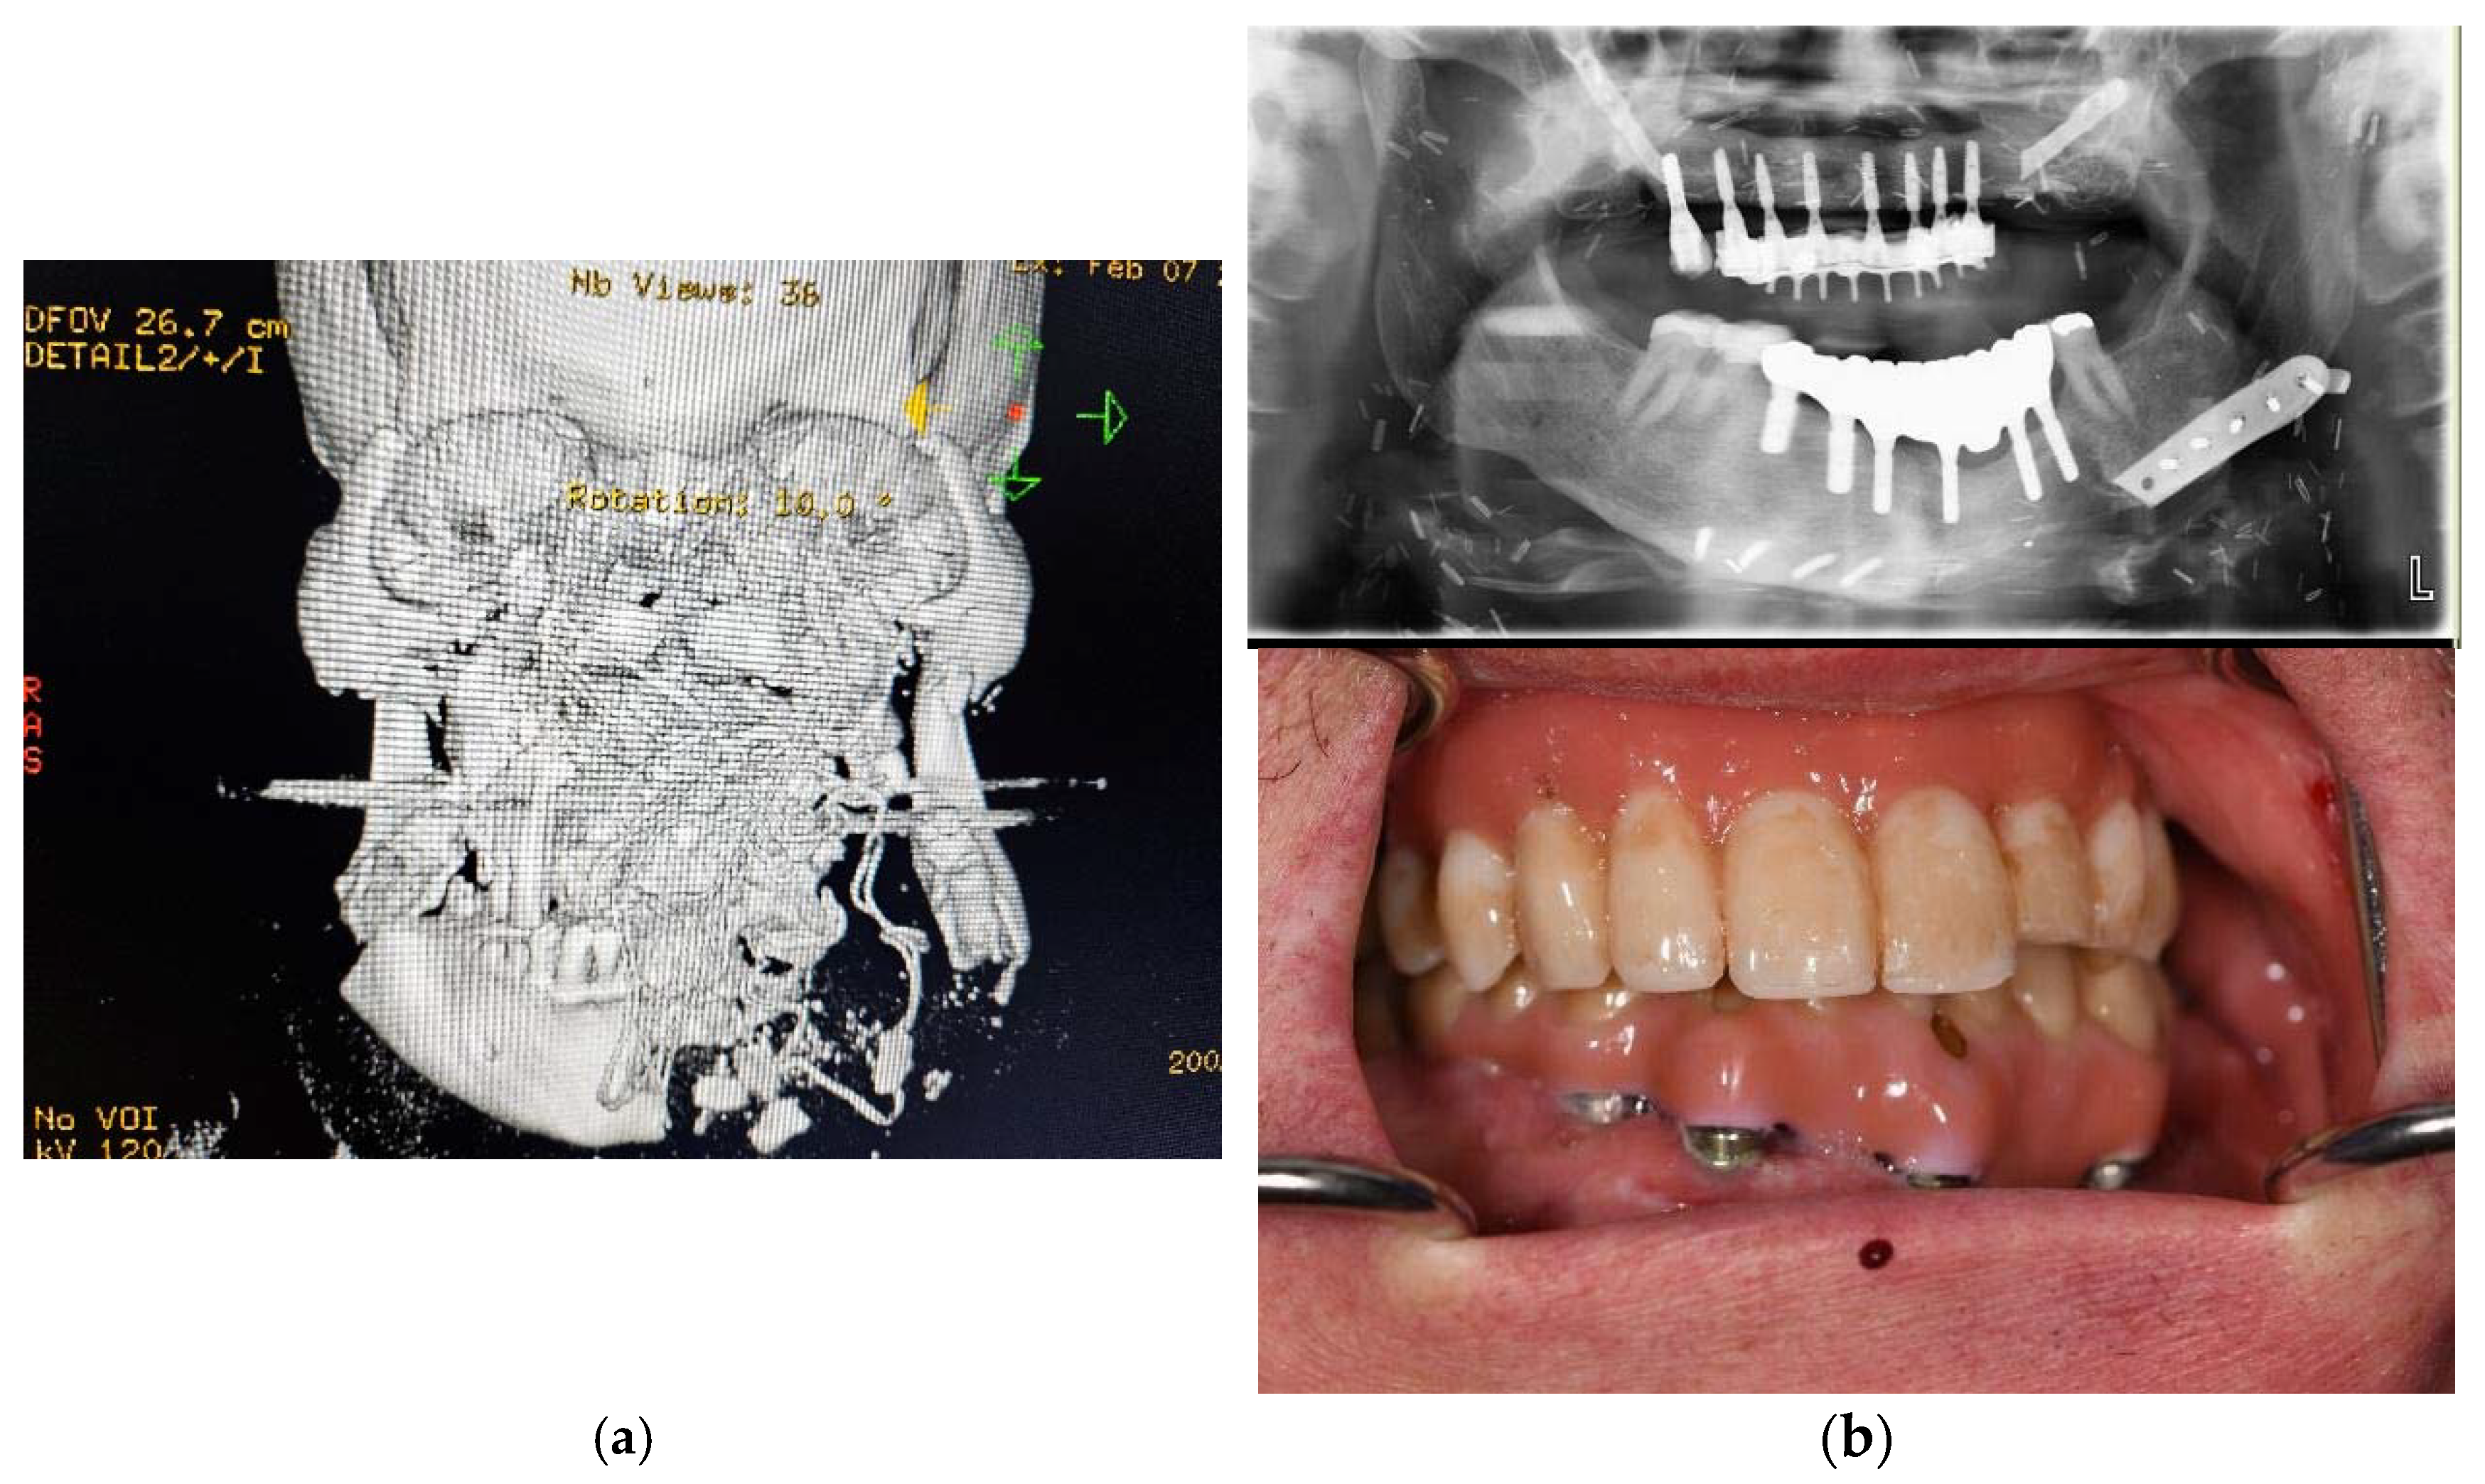

Figure 2.

Primary computed tomography (CT) of patient no. 6 upon arrival (a). Most of the maxilla and nasal structures are missing, the outer frame of the zygomatic bones have comminuted fracture, and the mandible has comminuted fracture as well as some missing parts. The bleeding was tamponated with cloth, and the radio-opague marking of the tissue can be seen in the 3D reconstruction. The missing bone in the maxilla and mandible of the patient no. 6 had been reconstructed earlier with vascularized bone using microvascular free flap positioned in the desired vertical and horizontal position using virtual planning and CAM-produced osteosynthesis (Planmeca Promodel, Helsinki, Finland). The custom osteosynthesis from the reconstructed maxilla had been mostly removed for dental reconstruction (upper b). The final dental rehabilitation involved a two-in-one structure in the maxilla and a conventional implant bridge in the mandible (lower b).